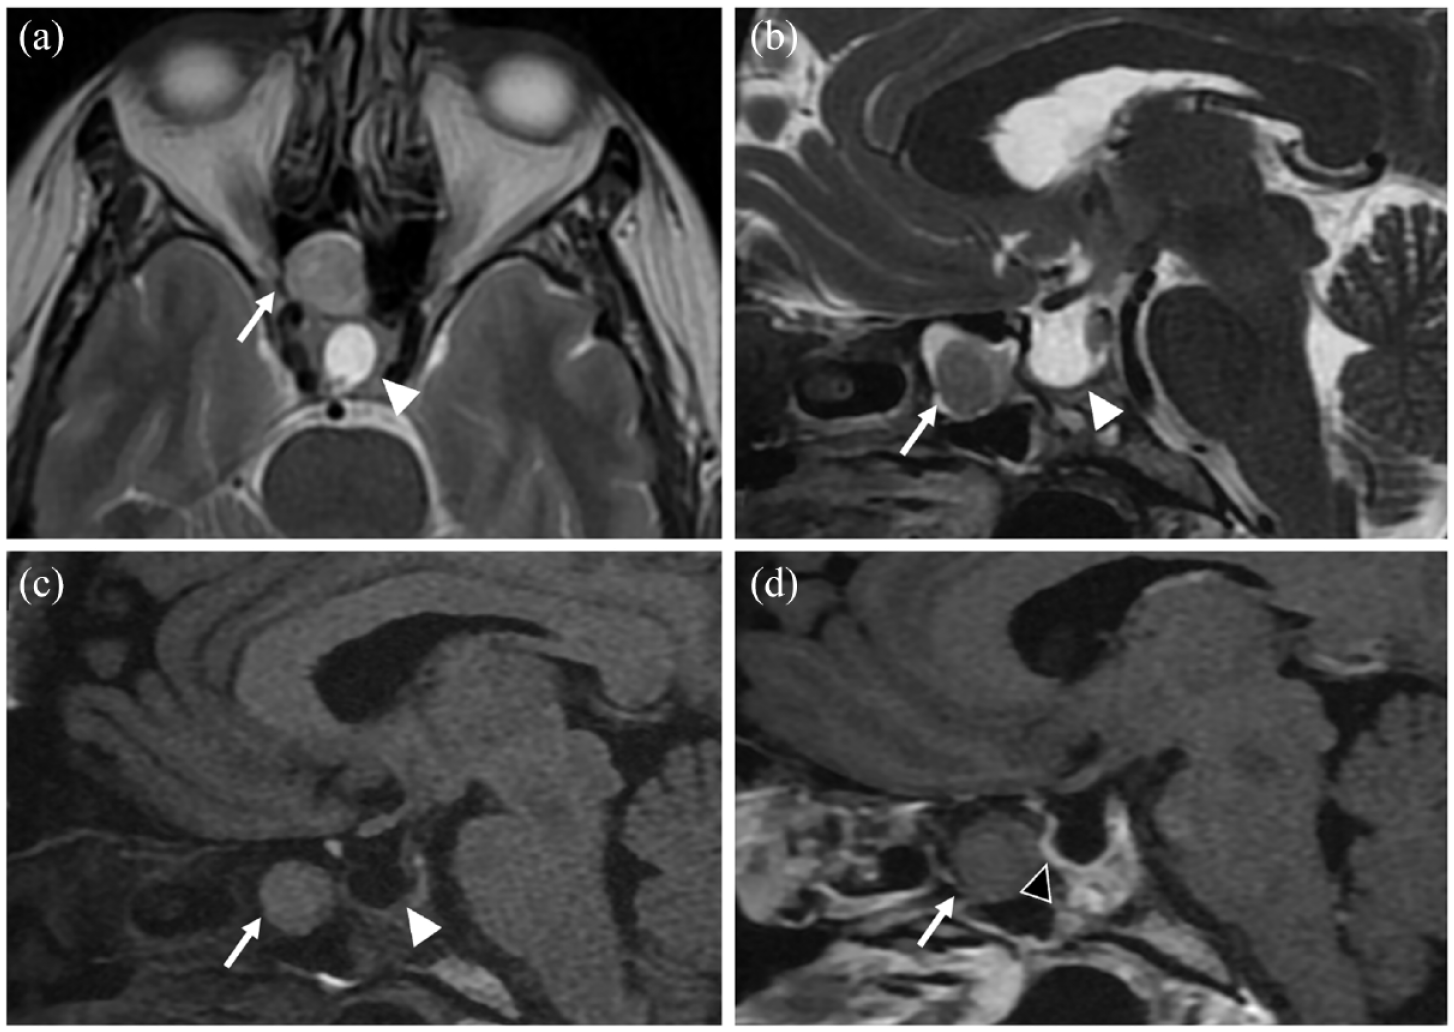

Subsequently, a Magnetic resonance imaging (MRI) was requested to rule out a pituitary adenoma. It revealed a space-occupying mass involving the SS with an iso-signal on T1 and a slight hypersignal on T2-weighted sequence (compared to white matter) (Figure 1). The mass did not invade the walls of the SS nor the sella tucica floor; however, it was causing obstruction of the SS ostium with mucus retention (Figure 2). Additionally, the MRI showed an intact pituitary stalk which traverse a cerebrospinal fluid filled sella (infundibulum sign) with no pituitary gland visualized. Dynamic contrast-enhanced sequences were performed, demonstrating a normal enhancement of the pituitary stalk with the absence of intra-sellar pituitary parenchyma. The ectopic adenoma exhibited a low enhancement, with no visualization of the normal pituitary parenchyma around it. This observation aligns with the classical characteristics of macroadenomas, where the pituitary parenchyma is excessively stretched and thinned to the point of being imperceptible. (Figures 3 and 4).

Axial T2-weighted image (a) and sagittal T2 (b), T1 FLAIR (Fluid-attenuated inversion recovery) (c) and T1 Fat-Sat GD+ (d) images with a focus on the sellar and sphenoid sinus (SS) regions. Visualization of a space-occupying mass in the right SS (arrow), the sella turcica is empty, only filled with cerebrospinal fluid (White arrowhead) ((a)–(c)). The injected sequence (d) shows a very mild enhancement of the mass, and does not visualize any sella turcica floor defect (Black arrowhead), which was confirmed during the surgical procedure.